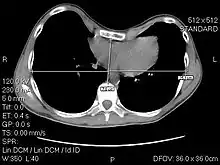

The Haller index, created in 1987 by J. Alex Haller, S. S. Kramer, and S. A. Lietman,[1] is a mathematical relationship that exists in a human chest section observed with a CT scan. It is defined as the ratio of the transverse diameter (the horizontal distance of the inside of the ribcage) and the anteroposterior diameter (the shortest distance between the vertebrae and sternum).[2]

where:

- HI is the Haller Index

- distance 1 is the distance of the inside ribcage (at the level of maximum deformity or at the lower third of the sternum)

- distance 2 is the distance between the sternal notch and vertebrae.